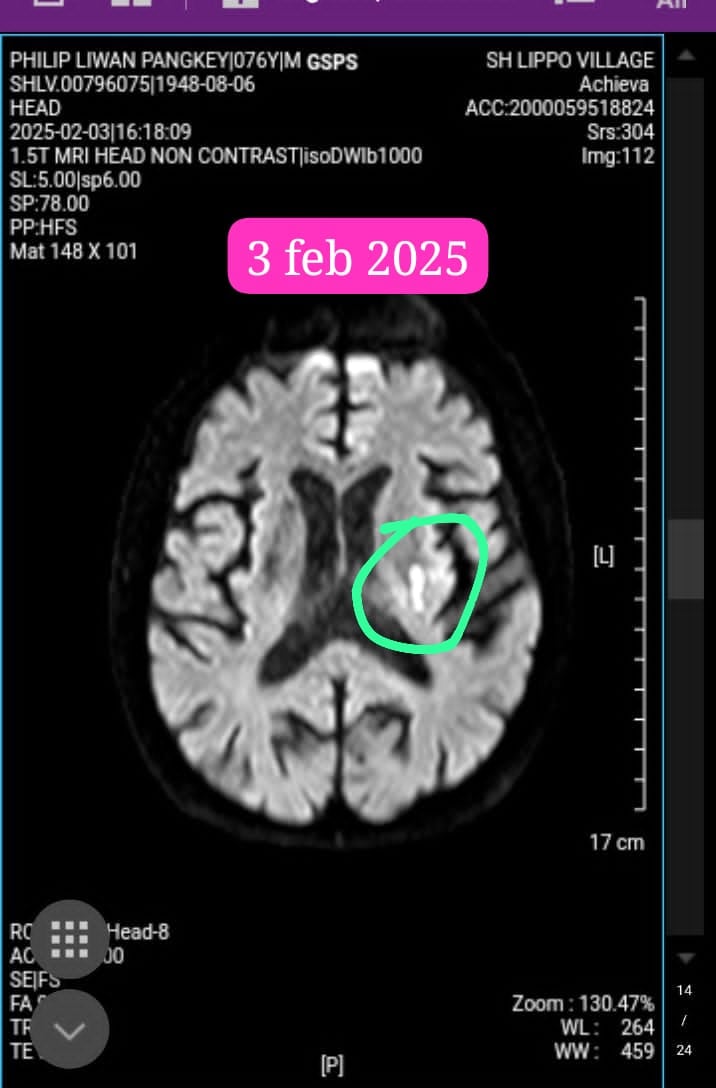

Februari 2025: Ujian Kedua

Belum sempat saya menarik napas lega, Papa terkena Stroke. Penggumpalan di otak kiri membuat tangan kanan Papa tidak bisa digerakkan, dan Papa kehilangan kemampuan untuk berjalan. Melihat sosok Ayah yang biasanya kuat dan mandiri tiba-tiba tidak berdaya adalah kesedihan yang sulit dilukiskan.